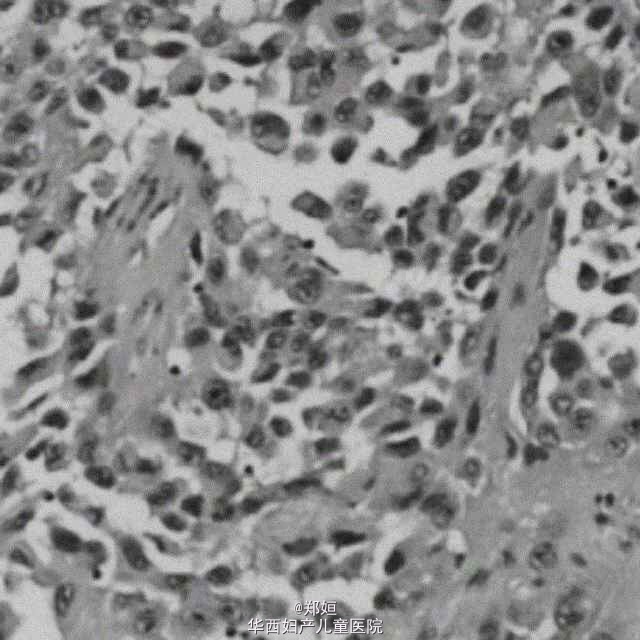

外阴棘层鳞状细胞癌

69岁女性,因外阴瘙痒1年和外阴外生性溃疡就诊。 溃疡位于双侧大小阴唇和阴阜,7*8cm,阴蒂尿道口正常。

诊断为外阴肿瘤 行外阴切除和双侧腹股沟淋巴结切除

随访1年后因盆腔肿瘤侵袭性占位死亡